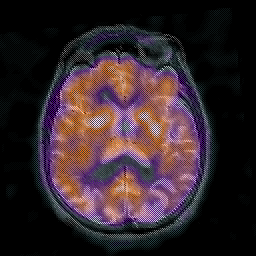

Alzheimer's disease: overlay -- Slice #30

[Home][Help][Clinical] Slice 30